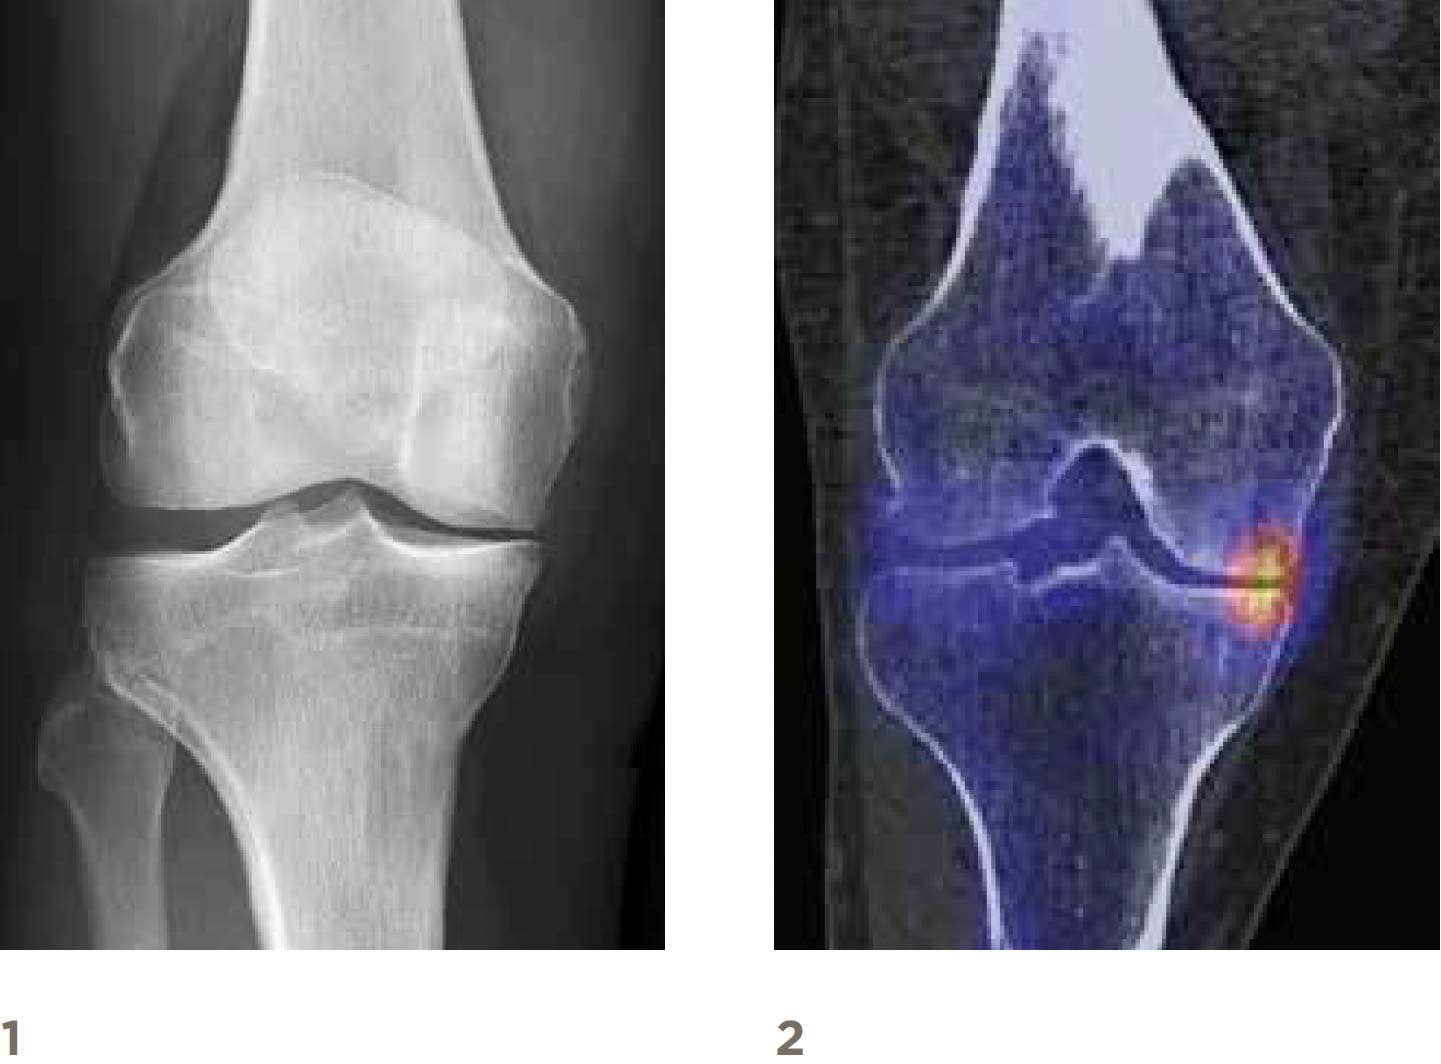

1 – X-ray right knee front view with narrowing of the joint space on the inside

2 – SPECT/CT right knee shows overload on the inside